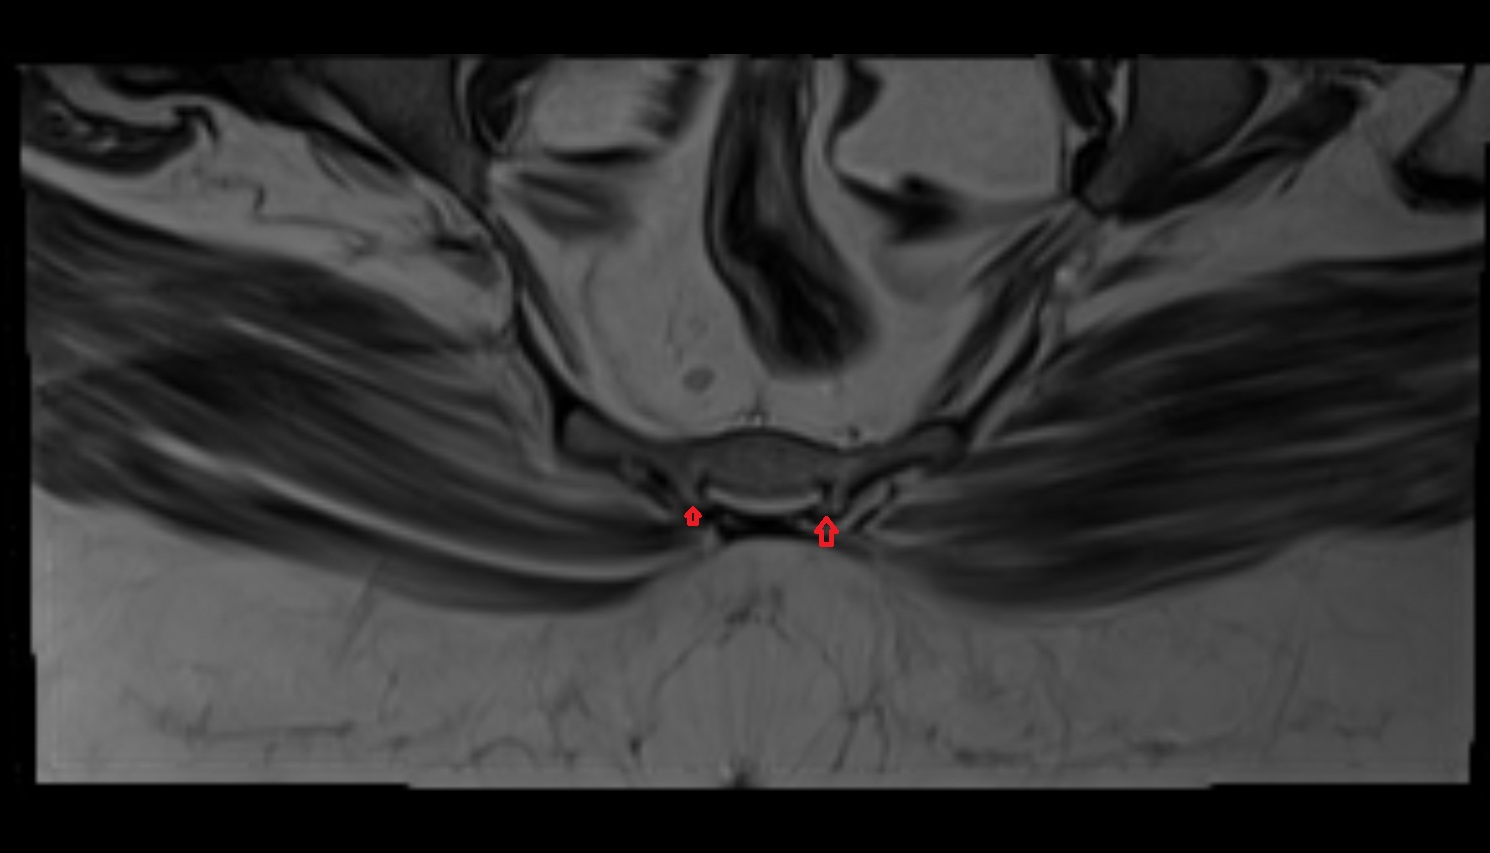

- Pubic symphysis